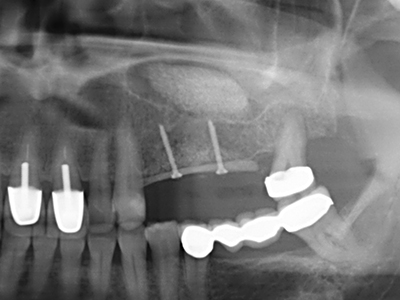

En la extracción de bloques óseos la piezocirugía también presenta ventajas adicionales: Además de la alta precisión en la osteotomía que ya se ha descrito antes, se ha comprobado que el uso de los delgados insertos de sierra resulta especialmente cuidadosas con el hueso. Frente a esto, sobre todo cuando se usan las fresas de Lindemann, cabe esperar pérdidas en la extracción significativamente más altas debido al mayor grosor de la parte frontal del cabezal (Lakshmiganthan, Gokulanathan et al. 2012). La separación basal que se necesita en particular en los injertos de bloque extraídos de forma retromolar se ve facilitada mediante sierras perpendiculares especialmente previstas a tal fin, lo que permite considerar que la cirugía piezoeléctrica es un procedimiento preciso y seguro para la obtención de bloques de hueso en el área retromolar (Happe 2007) (fig. 1-12).

Como ya se ha demostrado en el pasado, básicamente cualquier procedimiento de cirugía de hueso representa una posible indicación para la cirugía piezoeléctrica. Así, la preparación del segmento móvil en la osteogénesis de distracción (fig. 23-25) y en la osteotomía de sándwich puede realizarse con piezas especiales, sin poner en peligro el suministro sanguíneo de la parte crestal, que resulta esencial para el éxito de ambas técnicas (González-García, Diniz-Freitas et al. 2008).